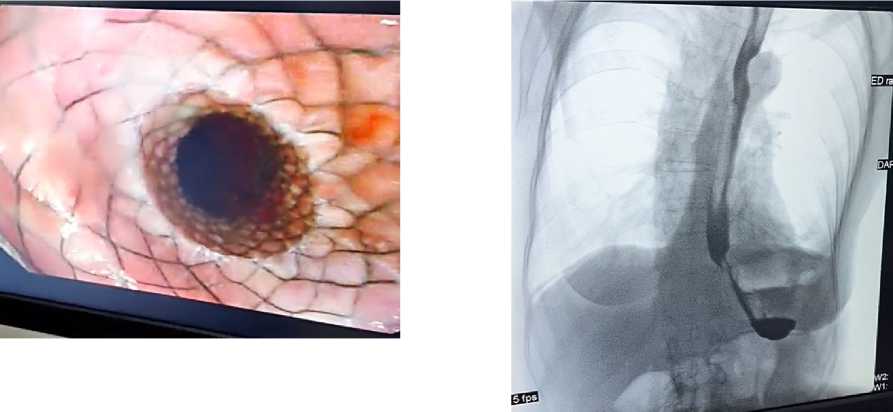

Эндоскопические методы лечения (бужирование и баллонная дилатация), применялись у всех пациентов как первый этап терапии. У большинства больных достигалось временное улучшение проходимости пищевода, однако при протяжённости рубцовой стриктуры более 3 см (Рисунок 1.) отмечалась высокая частота рецидива дисфагии.

Рисунок 1. Рентген снимок стриктуры пищевода с контрастным веществом

У 3 пациентов выполнена установка эндоскопического саморасширяющегося стента (Рисунок 2), что позволило временно стабилизировать состояние, однако не обеспечило долгосрочного эффекта. В случаях неэффективности минимально инвазивных методов пациентам выполнена тотальная торако-лапароскопическая экстирпация пищевода с замещением желудочным трансплантатом (Рисунок 3).

Рисунок 2. Пищеводный стент установленный эндоскопически

Рисунок 3. Рентгеноскопия пищевода с контрастным веществом